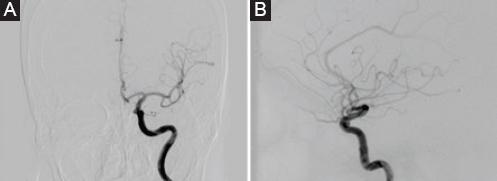

Mujer de 63 años con antecedente de artritis reumatoide en tratamiento. Presentó cefalea holocraneana pulsátil de 2 semanas de evolución acompañada de diplopía. En la exploración neurológica se encontró paresia del III nervio craneal izquierdo y resto sin alteraciones. Se realizaron estudios de imagen incluyendo angiografía con sustracción digital cerebral, y se identificó un aneurisma sacular pequeño de cuello amplio Barami tipo IIIb (Fig. 1).

Figura 1 A y B: angiografía con sustracción digital cerebral en la que se observa un aneurisma sacular pequeño de cuello amplio a nivel del cavum carotídeo con dirección ventromedial.